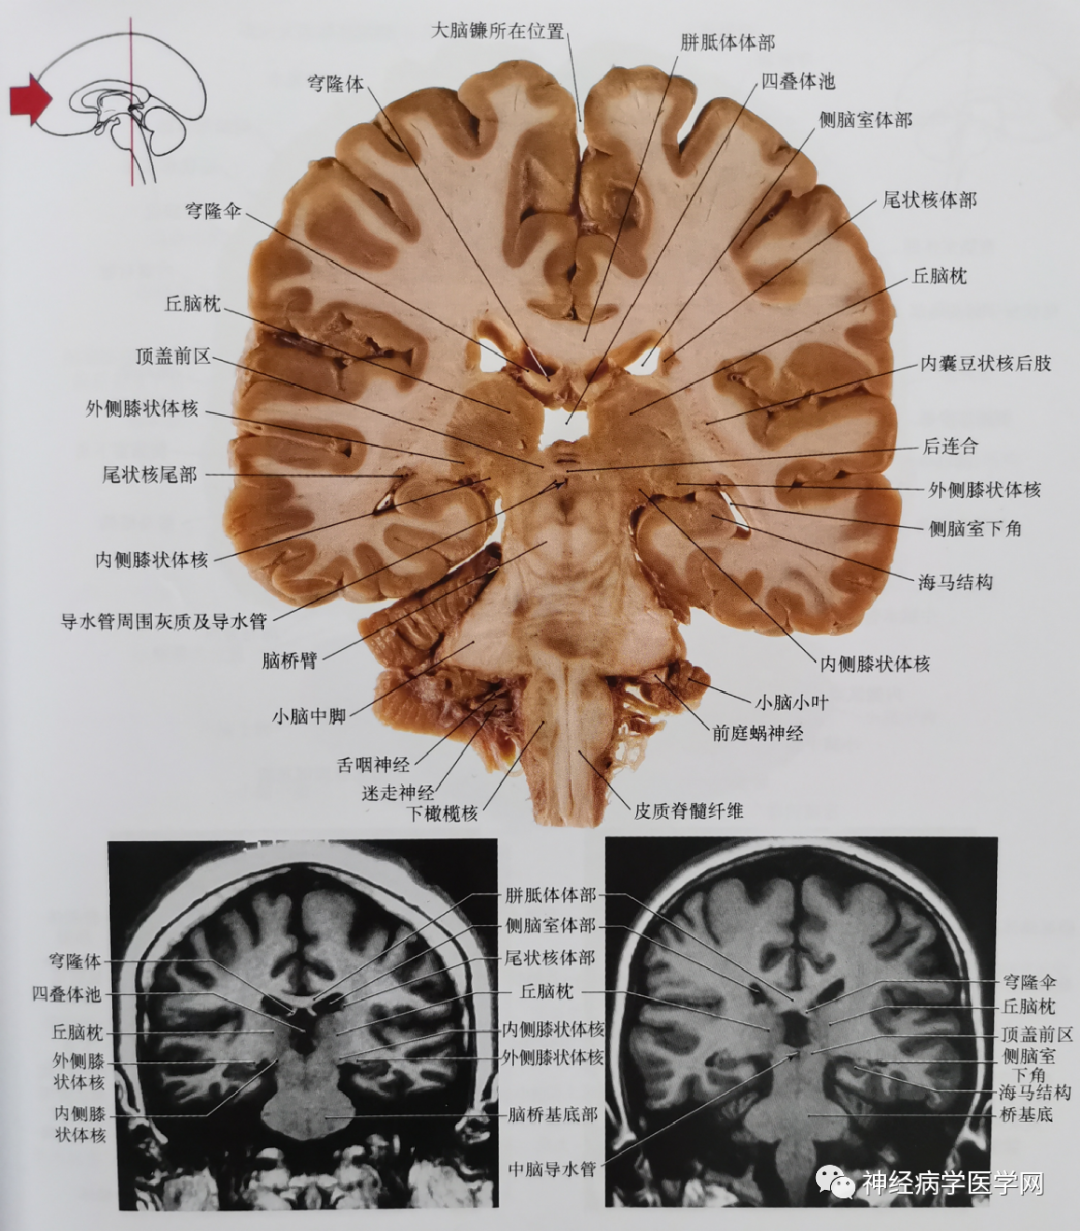

临床神经解剖图谱断层影像切片